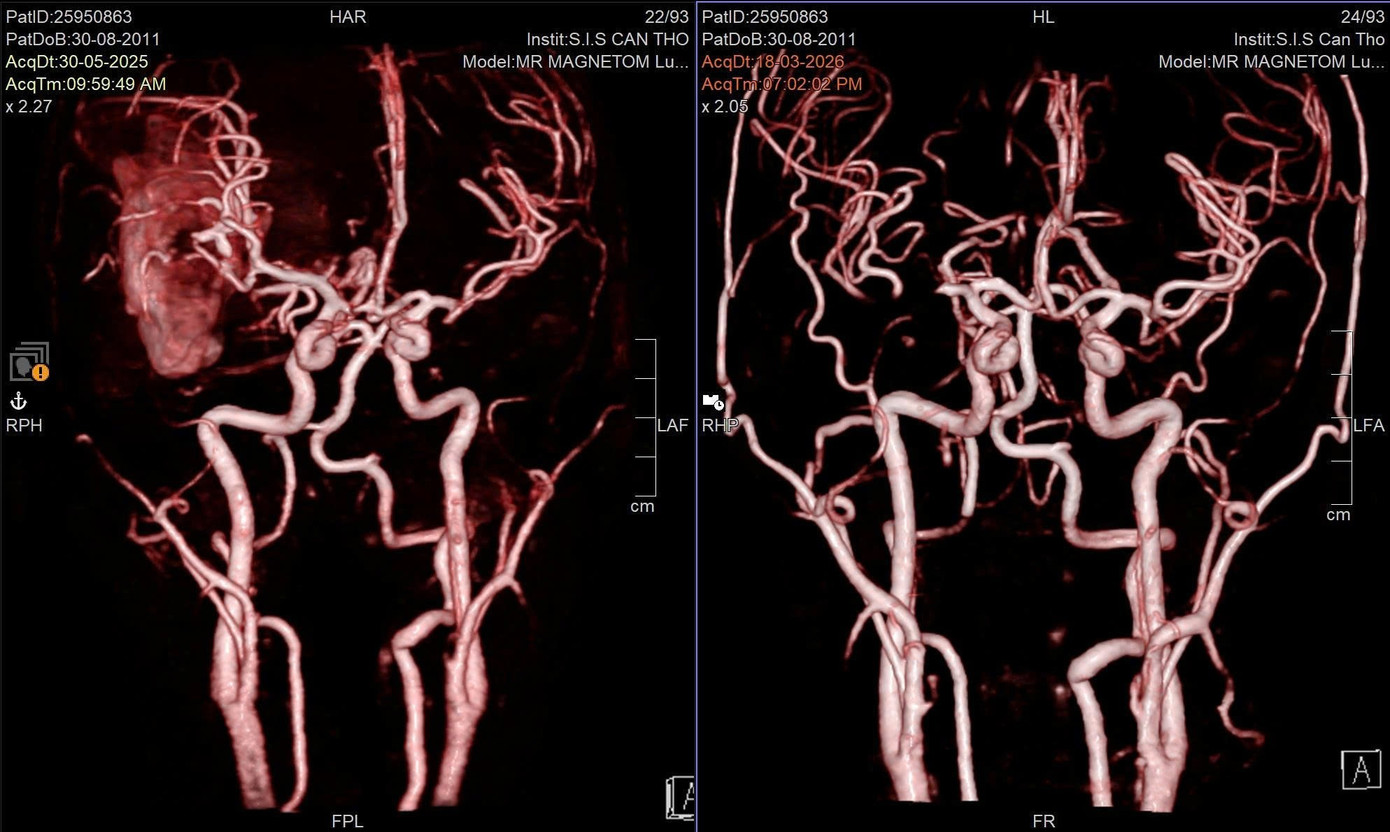

Cứu sống nam sinh hôn mê sâu do vỡ mạch máu não- Ảnh 2.

Sau quá trình điều trị và vật lý trị liệu phục hồi chức năng, em T. đã có thể cầm bút vẽ trở lại

Sau quá trình vật lý trị liệu, phục hồi chức năng, hiện sức khỏe của T. đã bình phục tốt. Từ tình trạng đối mặt với nguy cơ tử vong vì di chứng nặng nề, bệnh nhân đã có thể cầm bút vẽ trở lại. Theo đánh giá của bác sĩ, với tiến triển hiện tại, em có thể quay lại trường học trong năm học 2026–2027.